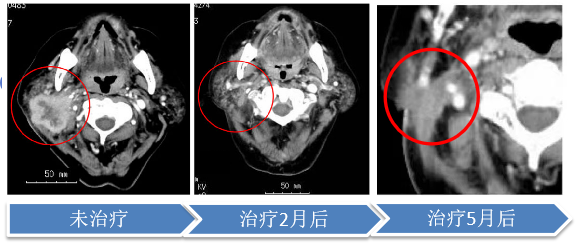

硼中子俘获治疗(BNCT)

硼中子俘获治疗(BNCT)是利用中子与肿瘤内硼元素发生核反应产生的次级粒子来摧毁癌细胞的一种放射性疗法。具有靶向性的硼药聚集在癌细胞周围,在中子的触发下,实施”定点爆破”,在细胞尺度上杀死癌细胞。与其他治疗手段相比,BNCT生物杀伤力高,生物靶向性高,达到了细胞级精准,对正常细胞伤害性小。仅需治疗1~2次(每次<1小时),远低于其他放疗(10~30次)和化疗(4~8个疗程,一个疗程21天)。其安全性高、疗程短、疗效显著、高壁垒的特点,吸引了美国、日本等国家加速布局。

目前首款硼药已经完成药理、药代及安全性相关的临床前研究,并计划于近期启动临床试验。同时,普利制药已成功构建了小分子硼药、ADC硼药、纳米硼药等技术平台,基于这些平台,成功研发了针对乳腺癌、脑胶质瘤等多种癌症的硼药系列产品,以期在BNCT和癌症治疗领域取得更为显著的成果。